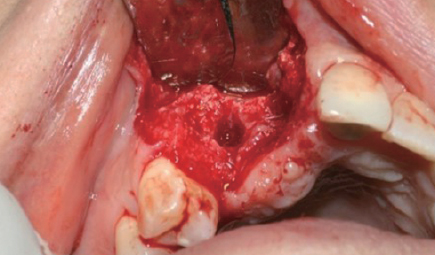

Case 1

Dr. 장호열

수술 전 파노라마

수술 전 구내 사진

판막 거상

식립 부위 천공

#43, 44, 45 & 46

Implant 식립

Wifi-Mesh 준비

Wifi-Mesh 형태 형성 *

Wifi-Mesh 장착

#33, 34, 35 & 36

절개(Releasing incision)

골 이식

Wifi-Mesh 위치시킴

Membrane holding suture

봉합

수술 후 파노라마

* 확실히 구부려 형태를 형성하여야 하며, 불완전하게 구부릴 경우 치은 안에서 벌어질 수 있습니다.